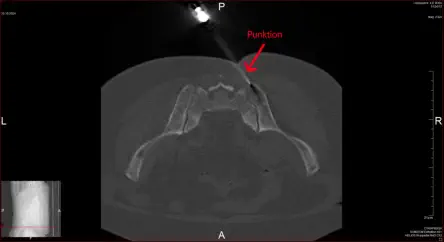

CT - Bilder der Punktion des Beckenkamm

Punktion

Punktion unter CT